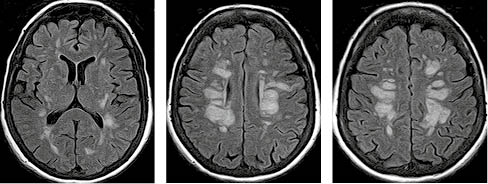

На рисунку 1 представлено МРТ-зображення головного мозку пацієнта з ГРЕМ у режимах Т2, Т2/Flair та Т1 із внутрішньовенним контрастуванням. Зокрема, візуалізуються двобічні вогнища округлої та овоїдної форми, гіперінтенсивні в режимах Т2 та Т2/Flair, які в більшості випадків накопичують контраст.

/images/nn257-1622023r1_.jpg)